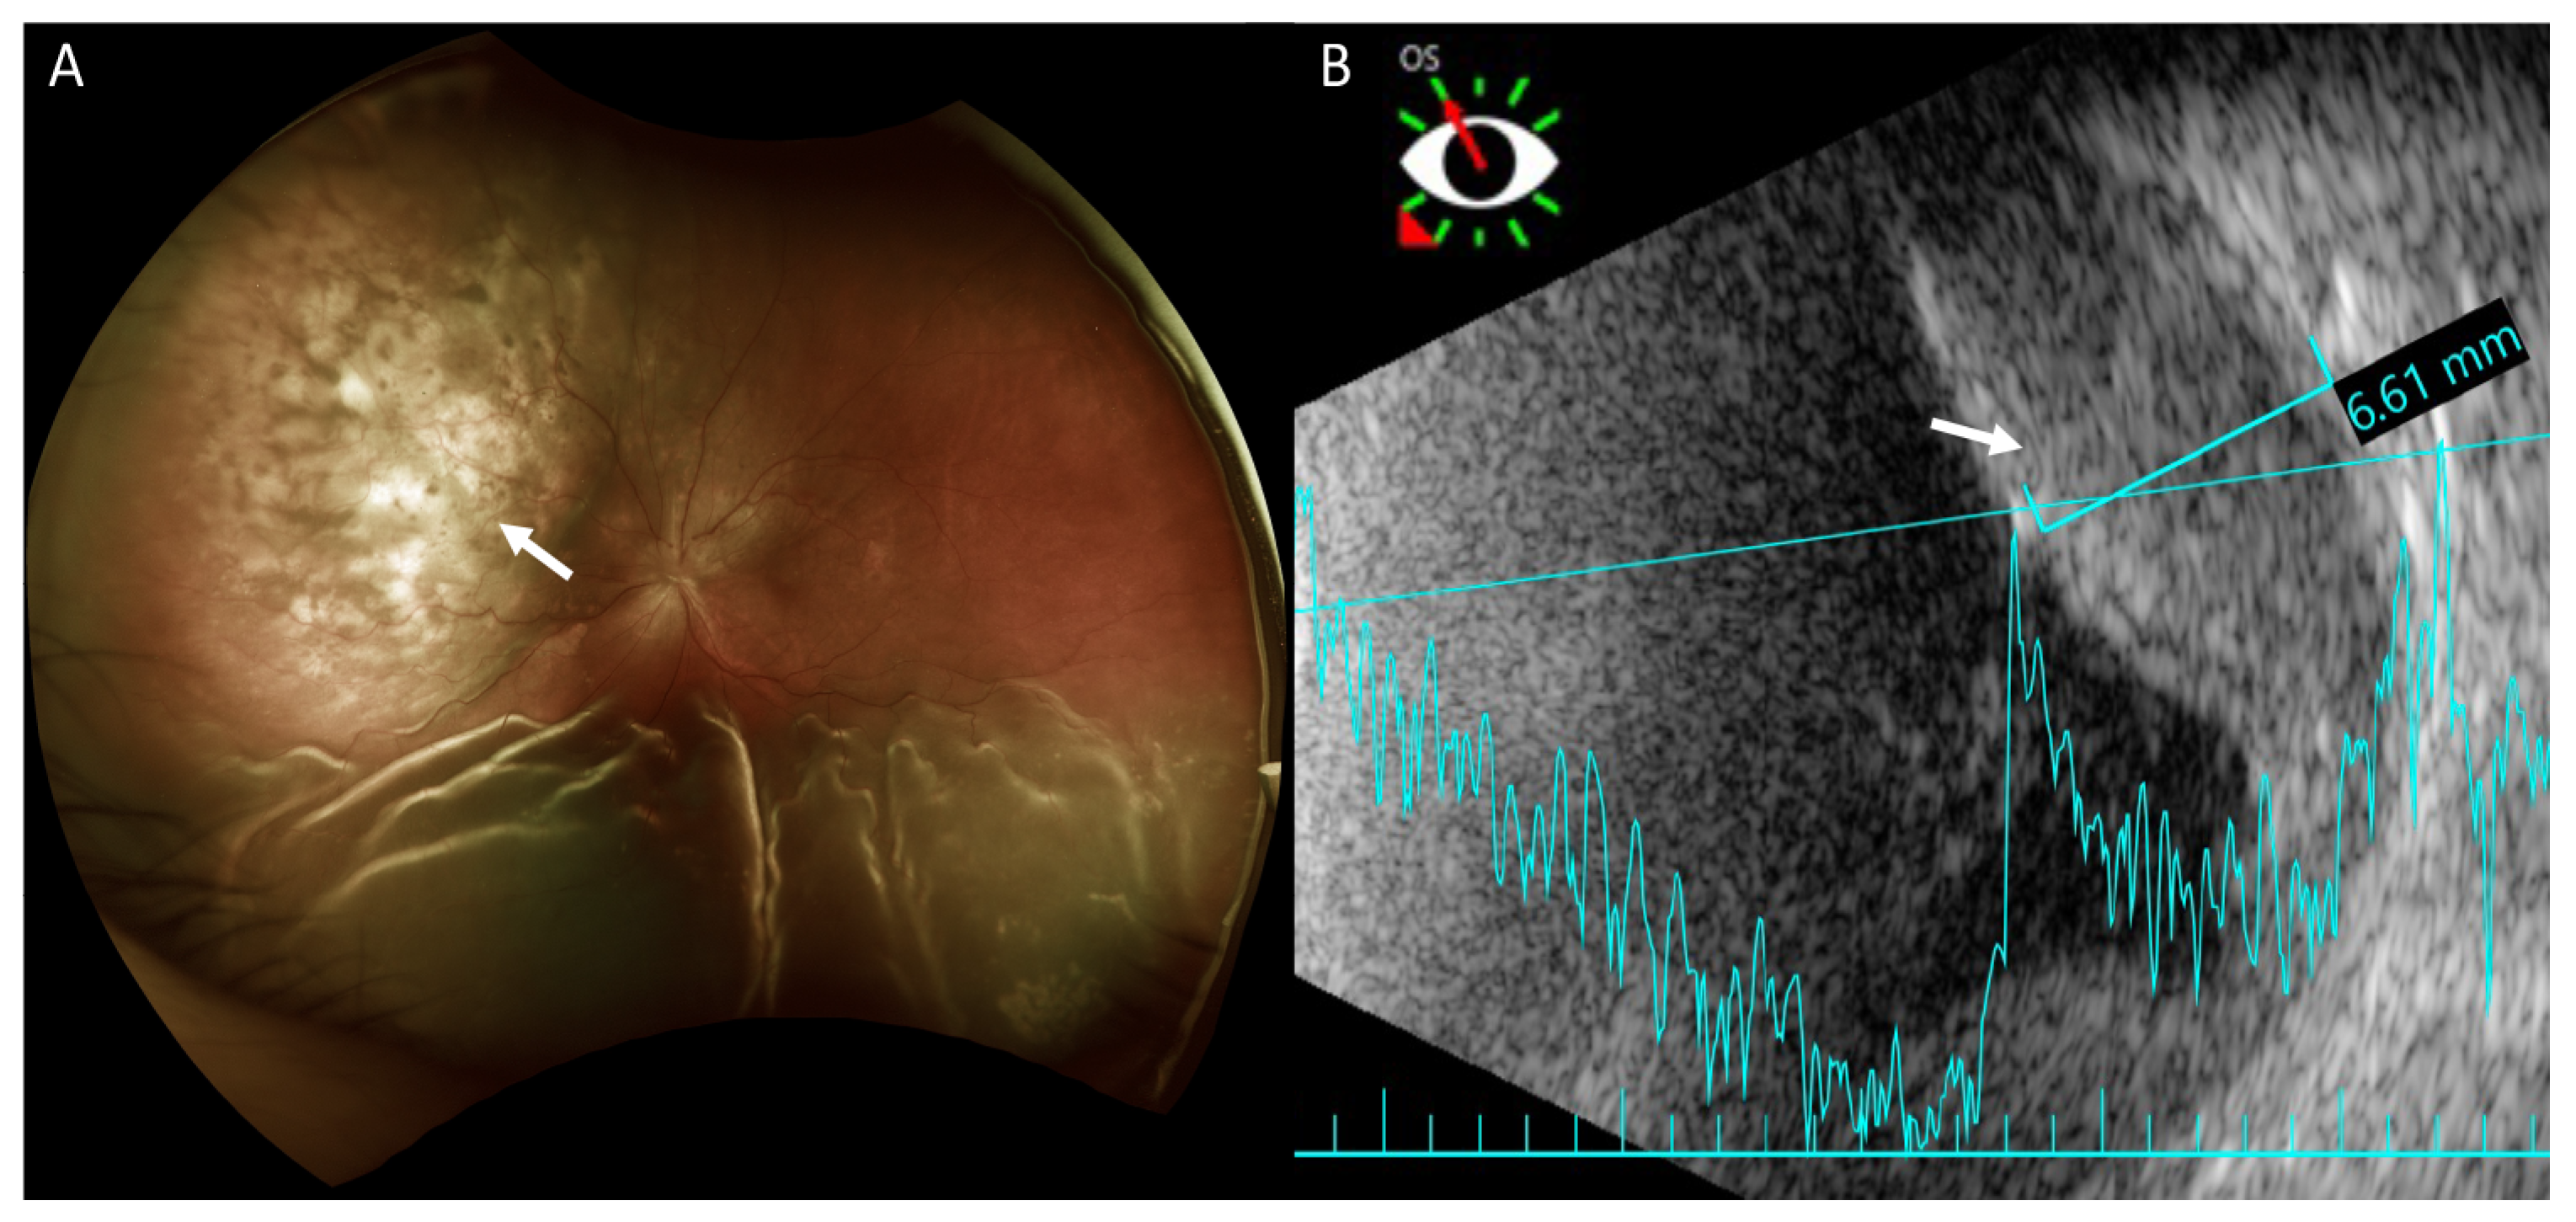

Fundus examination revealed retinal detachment mainly in the inferior region and an amelanotic choroidal mass with retinal detachment in the superior quadrant of her left eye (Figure 2A). Ultrasonography showed that this achromic choroidal mass was a hyperechoic lesion in the subretinal region with a thickness of approximately 6.61 mm, raising the possibility of intraocular tumor or metastasis (Figure 2B).

Figure 2.

Fundus photography and B-scan ultrasonography of the left eye. (A) Fundus photography shows exudative retinal detachment in the inferior retina and an amelanotic choroidal mass in the superior quadrant (arrow) in marked relief. Exudative retinal detachment is seen mainly on the sides of the choroidal mass. (B) Ultrasonography shows the achromic mass in the superior region as a hyperechoic lesion in the subretinal region (arrow) with a thickness of approximately 6.61 mm.

On fluorescein angiography (FA) and indocyanine green angiography (ICG), we observed hypofluorescence throughout the phases in the superior and inferior regions of the left eye. As there was only one mass on the fundus, this suggested that the hypofluorescence was partly related to the choroidal mass and partly to the ERD. Additionally, two hypofluorescent spots were noted in the temporal region of the fovea (Figure 3). These two small hypofluorescent spots were barely visible as orange-colored lesions on fundus examination (Figure 2A) and exhibited hypofluorescence throughout the angiography. These could be small choroidal metastatic lesions. The presence of these multifocal lesions supported the diagnosis of choroidal metastasis rather than choroidal melanoma or choroidal angioma, which are almost always unifocal.

Examinations to support the diagnosis of choroidal metastasis include fundus examination, ultrasonography, FA, ICG, and optical coherence tomography [2]. Furthermore, magnetic resonance imaging of the brain and orbit can rule out any coexisting metastatic brain lesions. On fundus examination, choroid metastases usually appear as solid, spotted, and yellow lesions [10], similar to those observed in the superonasal region in our patient (Figure 2A). Ultrasonography provides the depth and dimensions of the lesion; however, the clinical appearance of choroid metastasis or primary tumors such as melanoma or hemangioma can be similar. Thus, investigating the growth pattern and histoarchitecture of choroid tumors is important, with metastatic tumors being more lobulated and having higher reflectivity than primary choroid melanomas [3]. It was difficult to determine if the choroid tumor was lobulated in our patient because the hyperechoic lesion was situated beneath the ERD. However, the lesion showed high reflectivity. Choroid tumors usually have a similar pattern on FA, with a hypofluorescent pattern in the early phase and heterogeneous hyperfluorescence in the late phase. In addition, pinpoint hyperfluorescence may occur [3]. Thus, it is difficult to confirm if the lesion is a choroid tumor, such as melanoma or choroid metastasis using FA. In our patient, because of ERD, we did not observe a heterogeneously hyperfluorescent pattern in the late phase. ICG could potentially help differentiate choroidal tumors. Early rapid filling with extreme hyperfluorescence within 1 min, and sometimes a late wash-out phenomenon is often present in choroidal hemangioma [11,12]. Choroidal melanoma has varied presentation but usually demonstrates slower filling and less hyperfluorescent intensity compared to choroidal hemangiomas. Visible intrinsic vascularization is seen in 66% of choroidal melanomas, but most are hypofluorescent throughout [12]. Choroidal metastasis usually appears hypofluorescent in all phases [3,12], as seen in our patient.